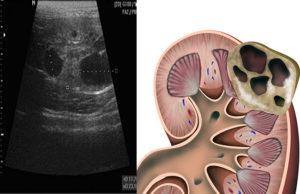

Эхогенность изменений паренхимы на УЗИ

Главным методом диагностирования патологического процесса, который поражает паренхиму, считается УЗИ.

Однако при трактовке результатов, которая проводится только специалистом, необходимо учитывать общее состояние больного.

А как понять, что с органами мочевыделения не все в порядке? Предположить какие-либо проблемы можно на основании жалоб больного, а вот точно оценить состояние почечной паренхимы позволит ультразвуковое исследование. Во время УЗИ врач определяет несколько параметров.

Эхогенность

Эхогенность – один из основных терминов ультразвуковой диагностики. Он отражает способность внутренних органов и тканей по-разному отражать сигнал, посылаемый УЗ-датчиком.

Жидкостные структуры и полости считаются анэхогенными (неэхогенными) и окрашены на экране монитора в черный цвет. Однако чем плотнее ткань, тем выше ее эхогенность.

Поэтому костные структуры выглядят на УЗИ как светлые, почти белые участки.

В норме органы мочевыделения имеют нормальную (среднюю) плотность. Если же эхогенность паренхимы почек повышена, это может свидетельствовать о развитии:

- гломерулонефрита;

- диабетической нефропатии;

- прочих обменных нарушений.

Структура

Еще один важный показатель УЗ-диагностики почек – структура их паренхимы. В норме она однородная, без патологических включений.